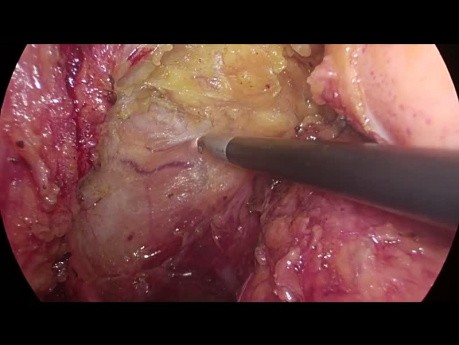

Colecistectomía laparoscópica en niño con hidrops...

Este video presenta una colecistectomía laparoscópica en un niño de 15 años con una inflamación masiva e hidropesía de la vesícula biliar.